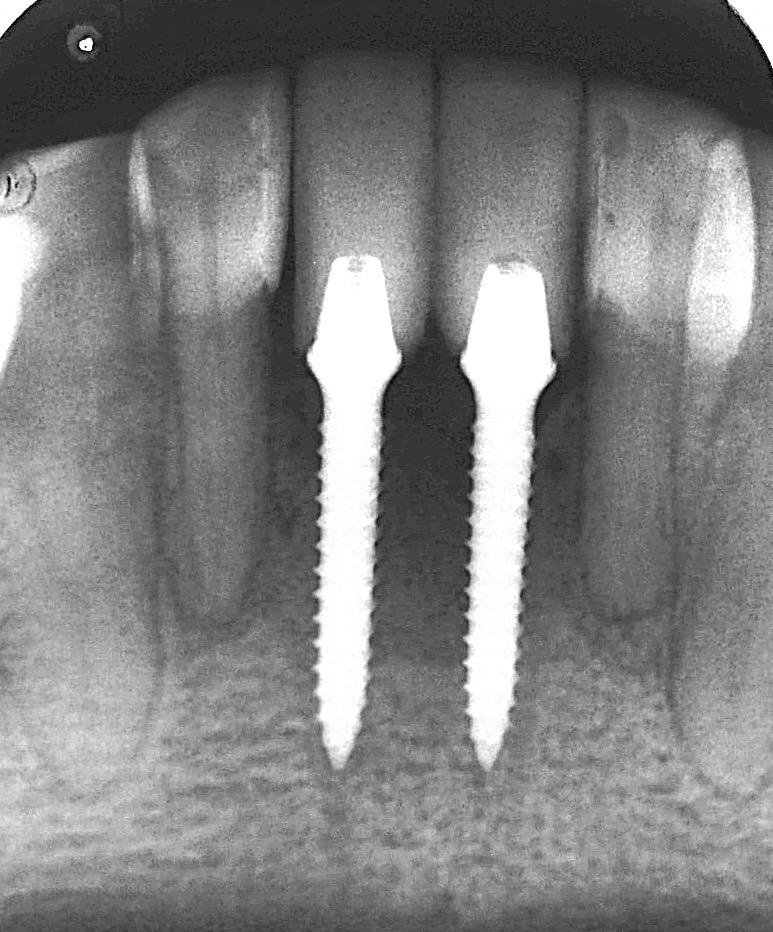

Com o avanço das pesquisas e das tecnologias de imagens, foi observado que na região dos incisivos centrais, a tábua óssea vestibular mesmo quando íntegra, era muito final, menor que 1mm em 70%, resultando em uma reabsorção de boa parte desta, mesmo com técnicas pouco traumáticas.

Por esta razão, para que o implante imediato estético tenha um resultado satisfatório, esta tábua óssea deve ter sua espessura aumentada para que mantenha-se estável.

Como é necessário sempre reconstruir a parede vestibular, sua integridade não se faz necessária. Manfro et al (2019) propuseram uma classificação para esta perda e de acordo com essa classificação modificações para a técnica cirúrgica.